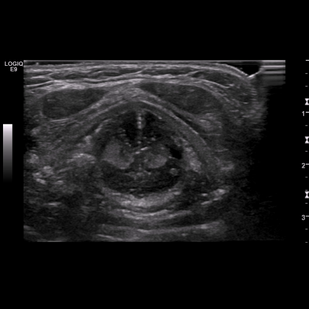

• Обложка: 1.2 Нормальная анатомия шеи и щитовидной железы в поперечном сечении